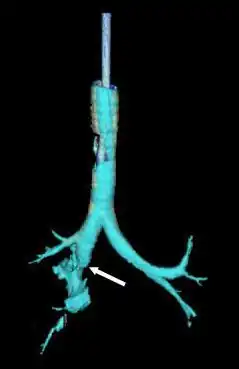

| Reconstruction of the trachea and bronchi with x-ray computed tomography showing disruption of the right main bronchus with abnormal lucency (arrow)[1] | |